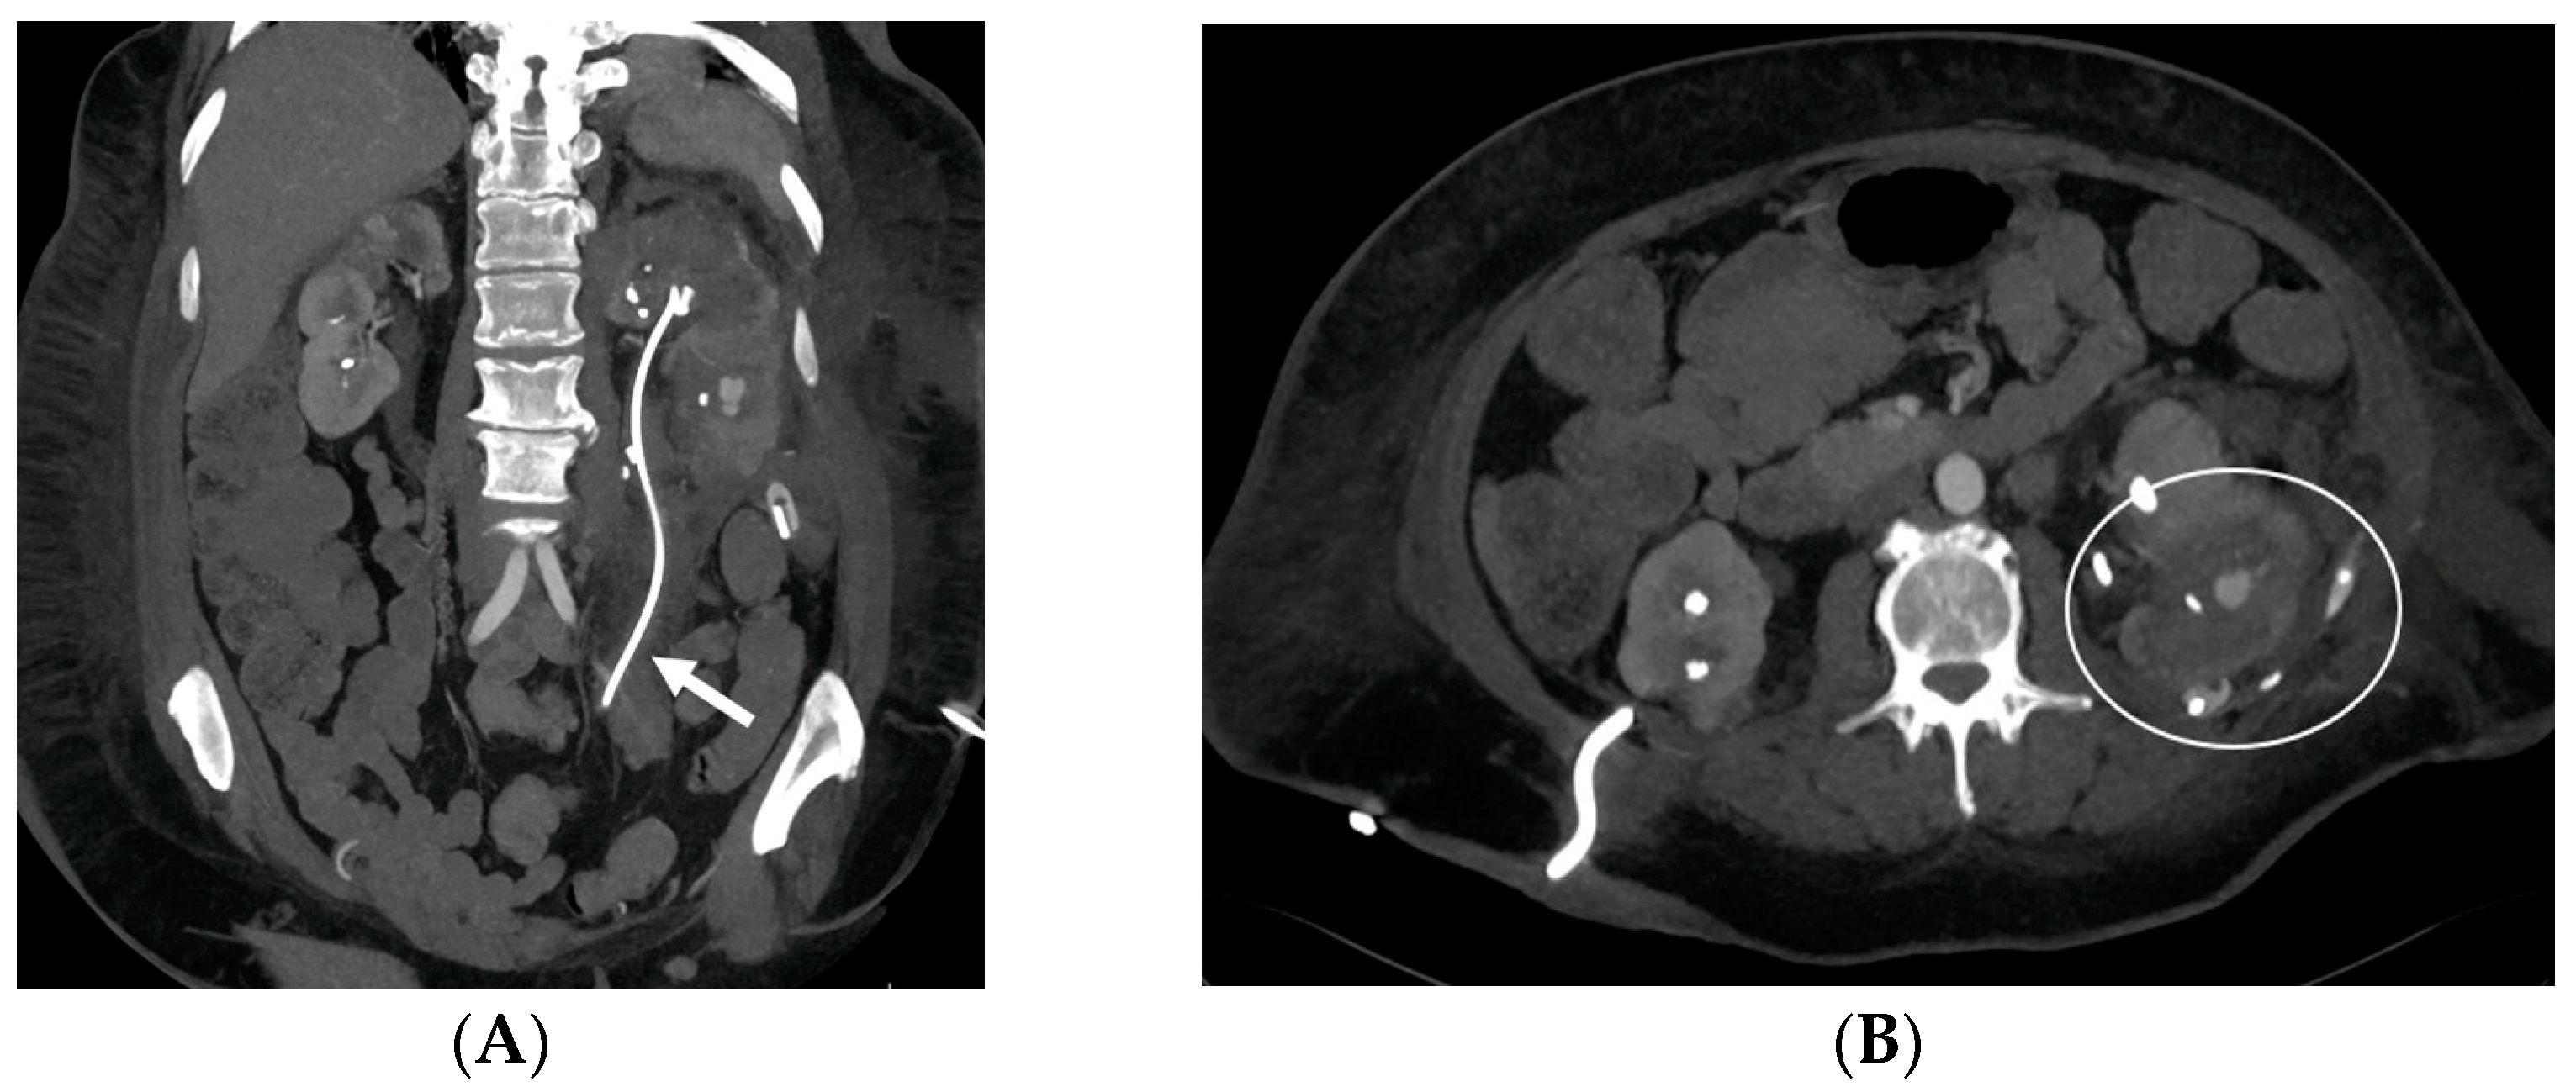

- Malposition: The malposition of a stent is defined as an incorrect position relative to initial placement, while displacement presents a subsequent occurrence in a device that was previously located in the correct position. A stent improperly positioned might assume a sub-pyelic position when the proximal end fails to reach the renal pelvis and a supravesical position when the distal end is detected within the ureter. The origins of this complication predominantly stem from the placement technique, whether it be endoscopy- or fluoroscopy-guided insertion. This underscores the need to verify the accurate positioning of the stent post-placement. Ensuring an adequate length is essential to reduce the occurrence of this complication (Figure 2, Figure 3, Figure 4, Figure 5 and Figure 6) [21,22].